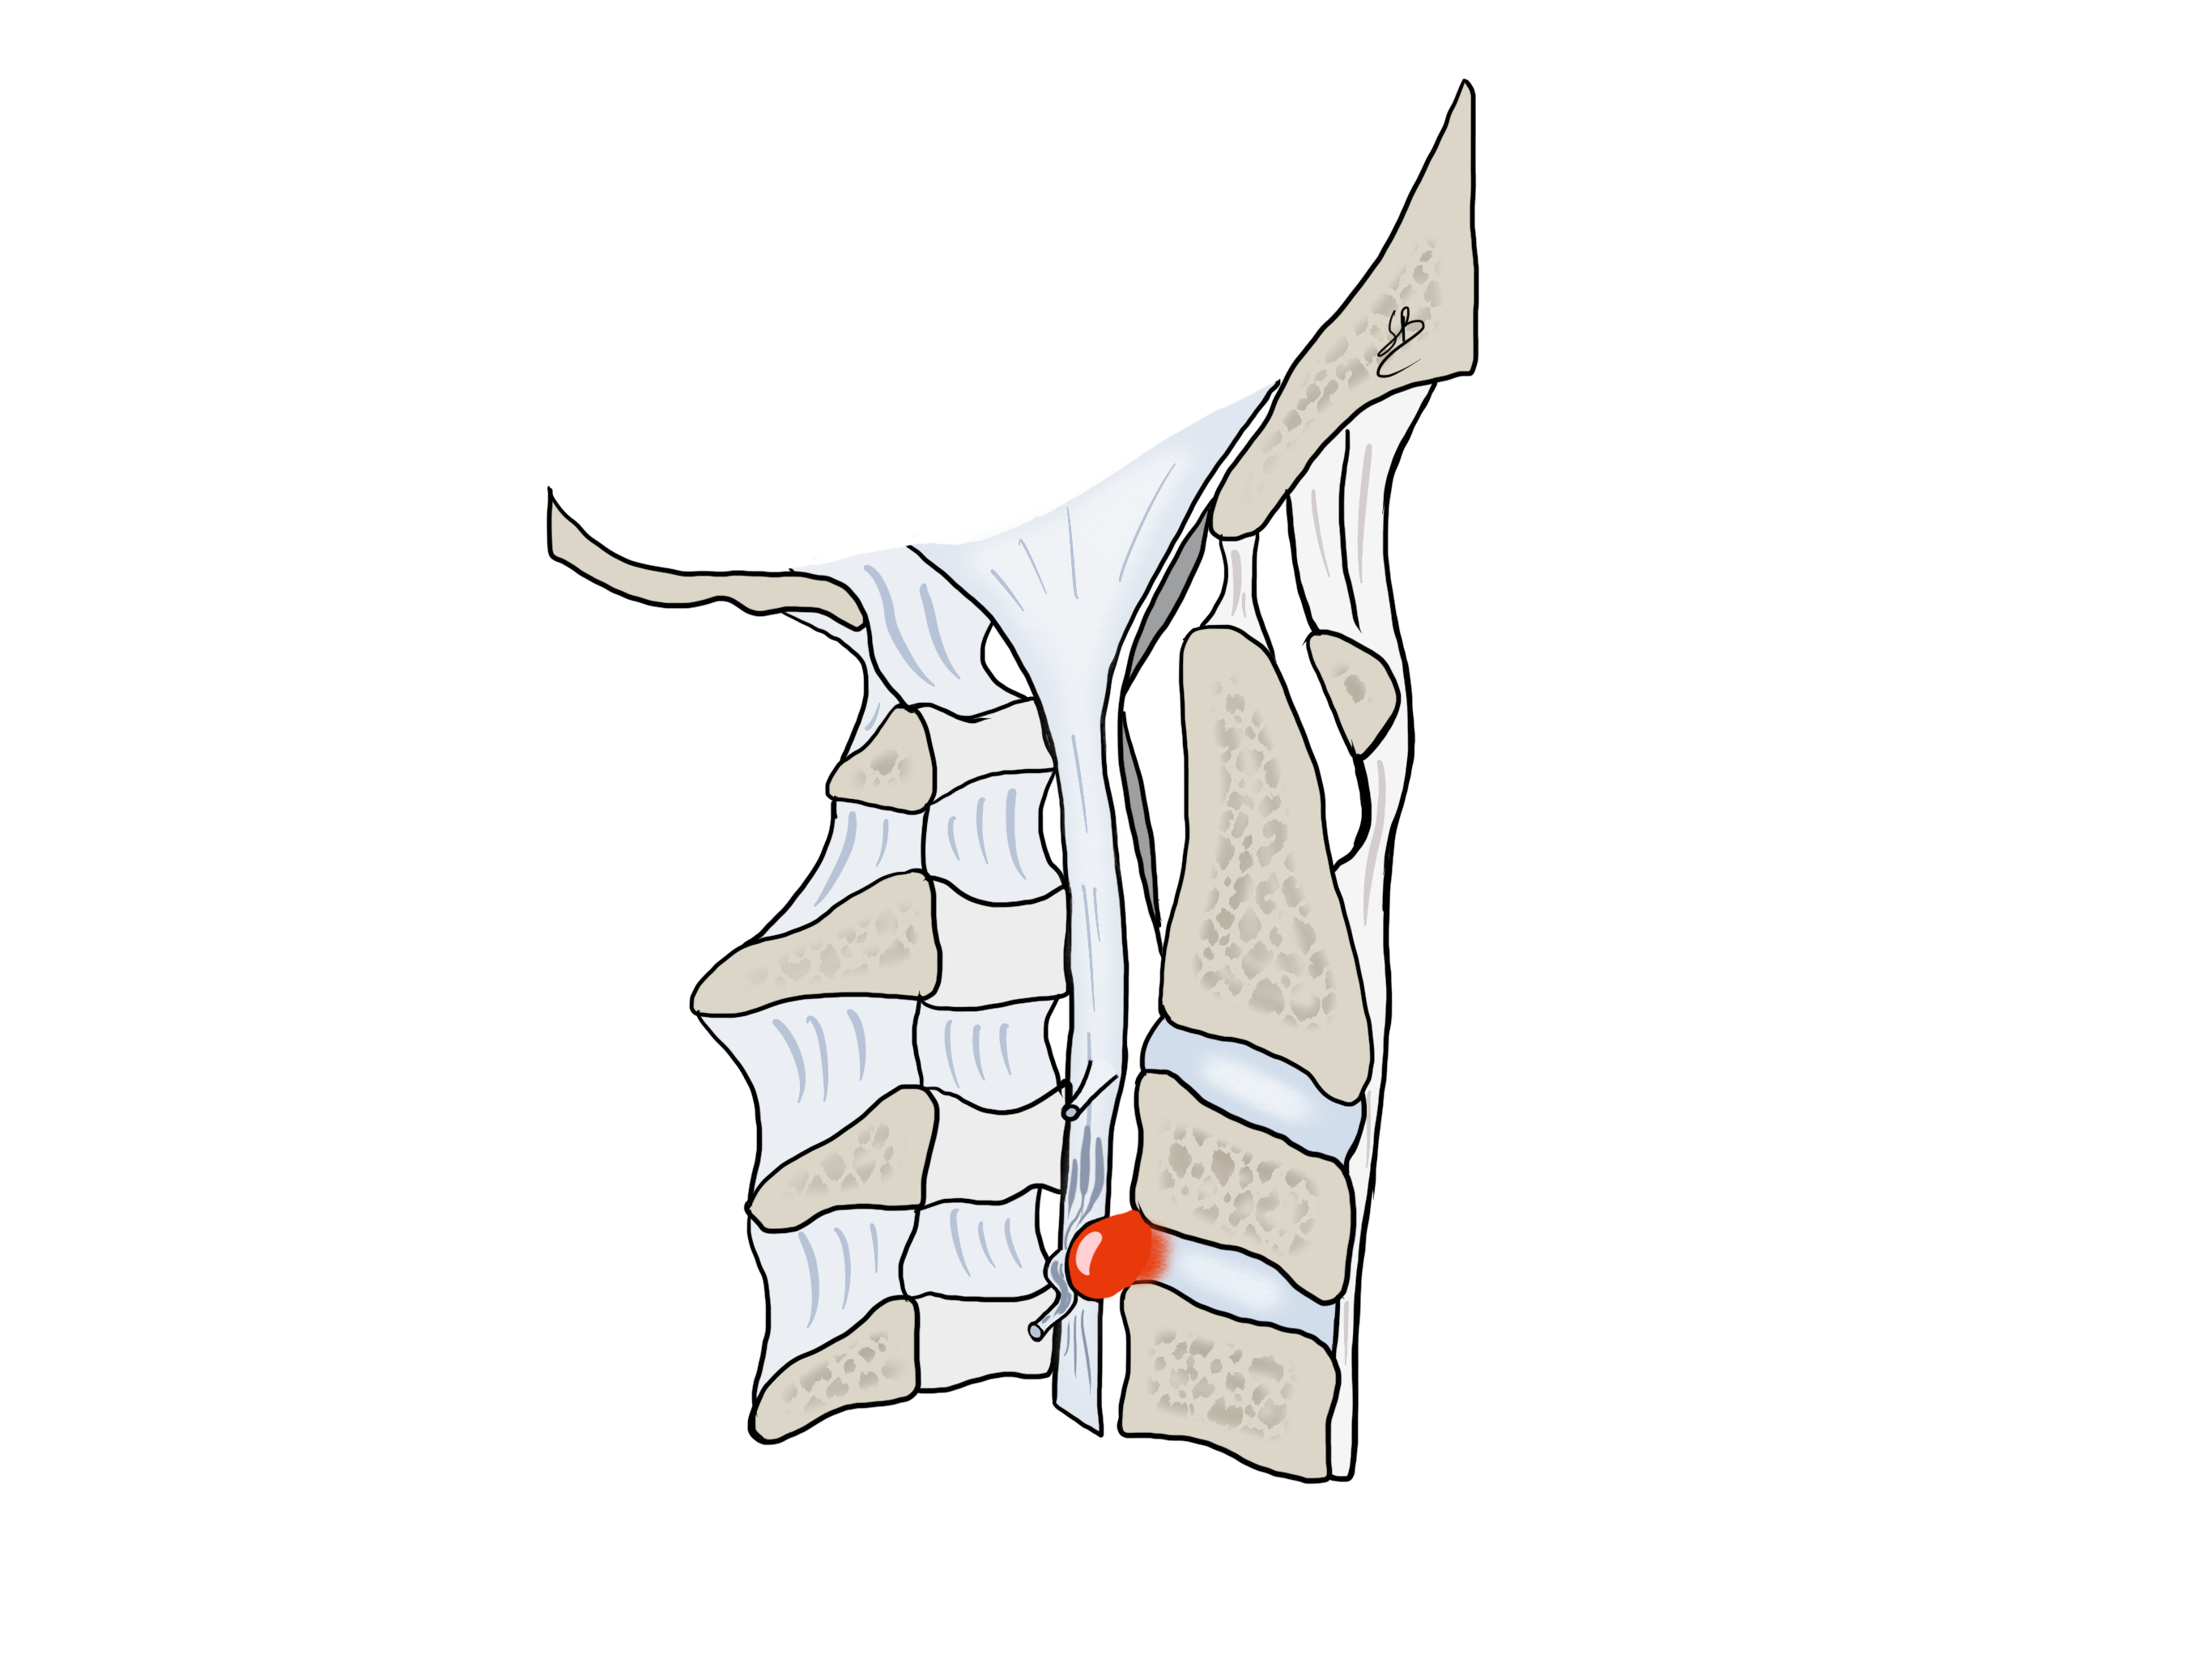

Une hernie discale cervicale peut soit comprimer un nerf allant dans le membre supérieur, soit comprimer la moelle épinière. Quand la hernie vient comprimer une racine nerveuse le ou la patient(e) présente alors une douleur radiculaire dans le bras dû à la souffrance ou à l’inflammation du nerf. En cas de compression de la moelle épinière, de graves problèmes neurologiques peuvent survenir comme une perte de la motricité des jambes, des bras ou même une incontinence, on parle de syndrome de myélopathie cervicale.

Hernie discale avec compressione radiculaire

Dans la plupart des cas, une hernie discale peut être traitée de façon conservative avec des traitements antalgiques, anti-inflammatoires ou par une infiltration autour du nerf comprimé. Tous ces traitements « conservateurs » ont pour but de diminuer ou d’éliminer l’inflammation du nerf. Ce traitement « conservateur » est contre-indiqué en cas de déficit moteur ou de syndrome de myélopathie cervicale.

Si les méthodes conservatives ne portent aucun bénéfice, l’intervention chirurgicale devient indiquée. Il s’agit alors d’une décompression du nerf en retirant la hernie discale par voie antérieure. Le disque malade est alors substitué par une petite cage en titane. L’intervention dure environ 1 heure, sous anesthésie générale. Le Dr Robert et la Dresse Bonasia réalisent ce type d’intervention de façon microscopique pour limiter au maximum l’ouverture cutanée (environ 3 cm) ainsi que pour diminuer le risque de lésion nerveuse. Ils présentent une expérience de cette technique de plus de 200 cas opérés.